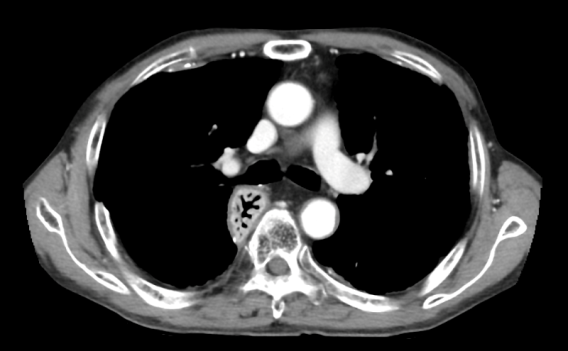

700床を超す著明な国立A病院で、肺がんの治療を受けていた建設大工Bさんの胸部CT写真が、写真1です。後から見れば、明らかな胸膜肥厚斑(胸膜プラーク)を認めますが、A病院の呼吸器内科医も放射線科医も認識していませんでした。

写真1 国立A病院のCT画像